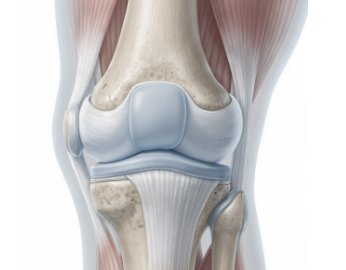

무릎 관절에는 충격을 흡수하는 연골이 있습니다.

연골이 약해지거나 마찰이 증가하면 움직일 때 소리가 발생할 수 있습니다.

이 경우 나이가 들면서 더 흔하게 나타날 수 있습니다.

4. 슬개골 위치 변화

무릎 앞쪽에 있는 슬개골(무릎뼈)의 움직임이 원활하지 않으면 소리가 날 수 있습니다.